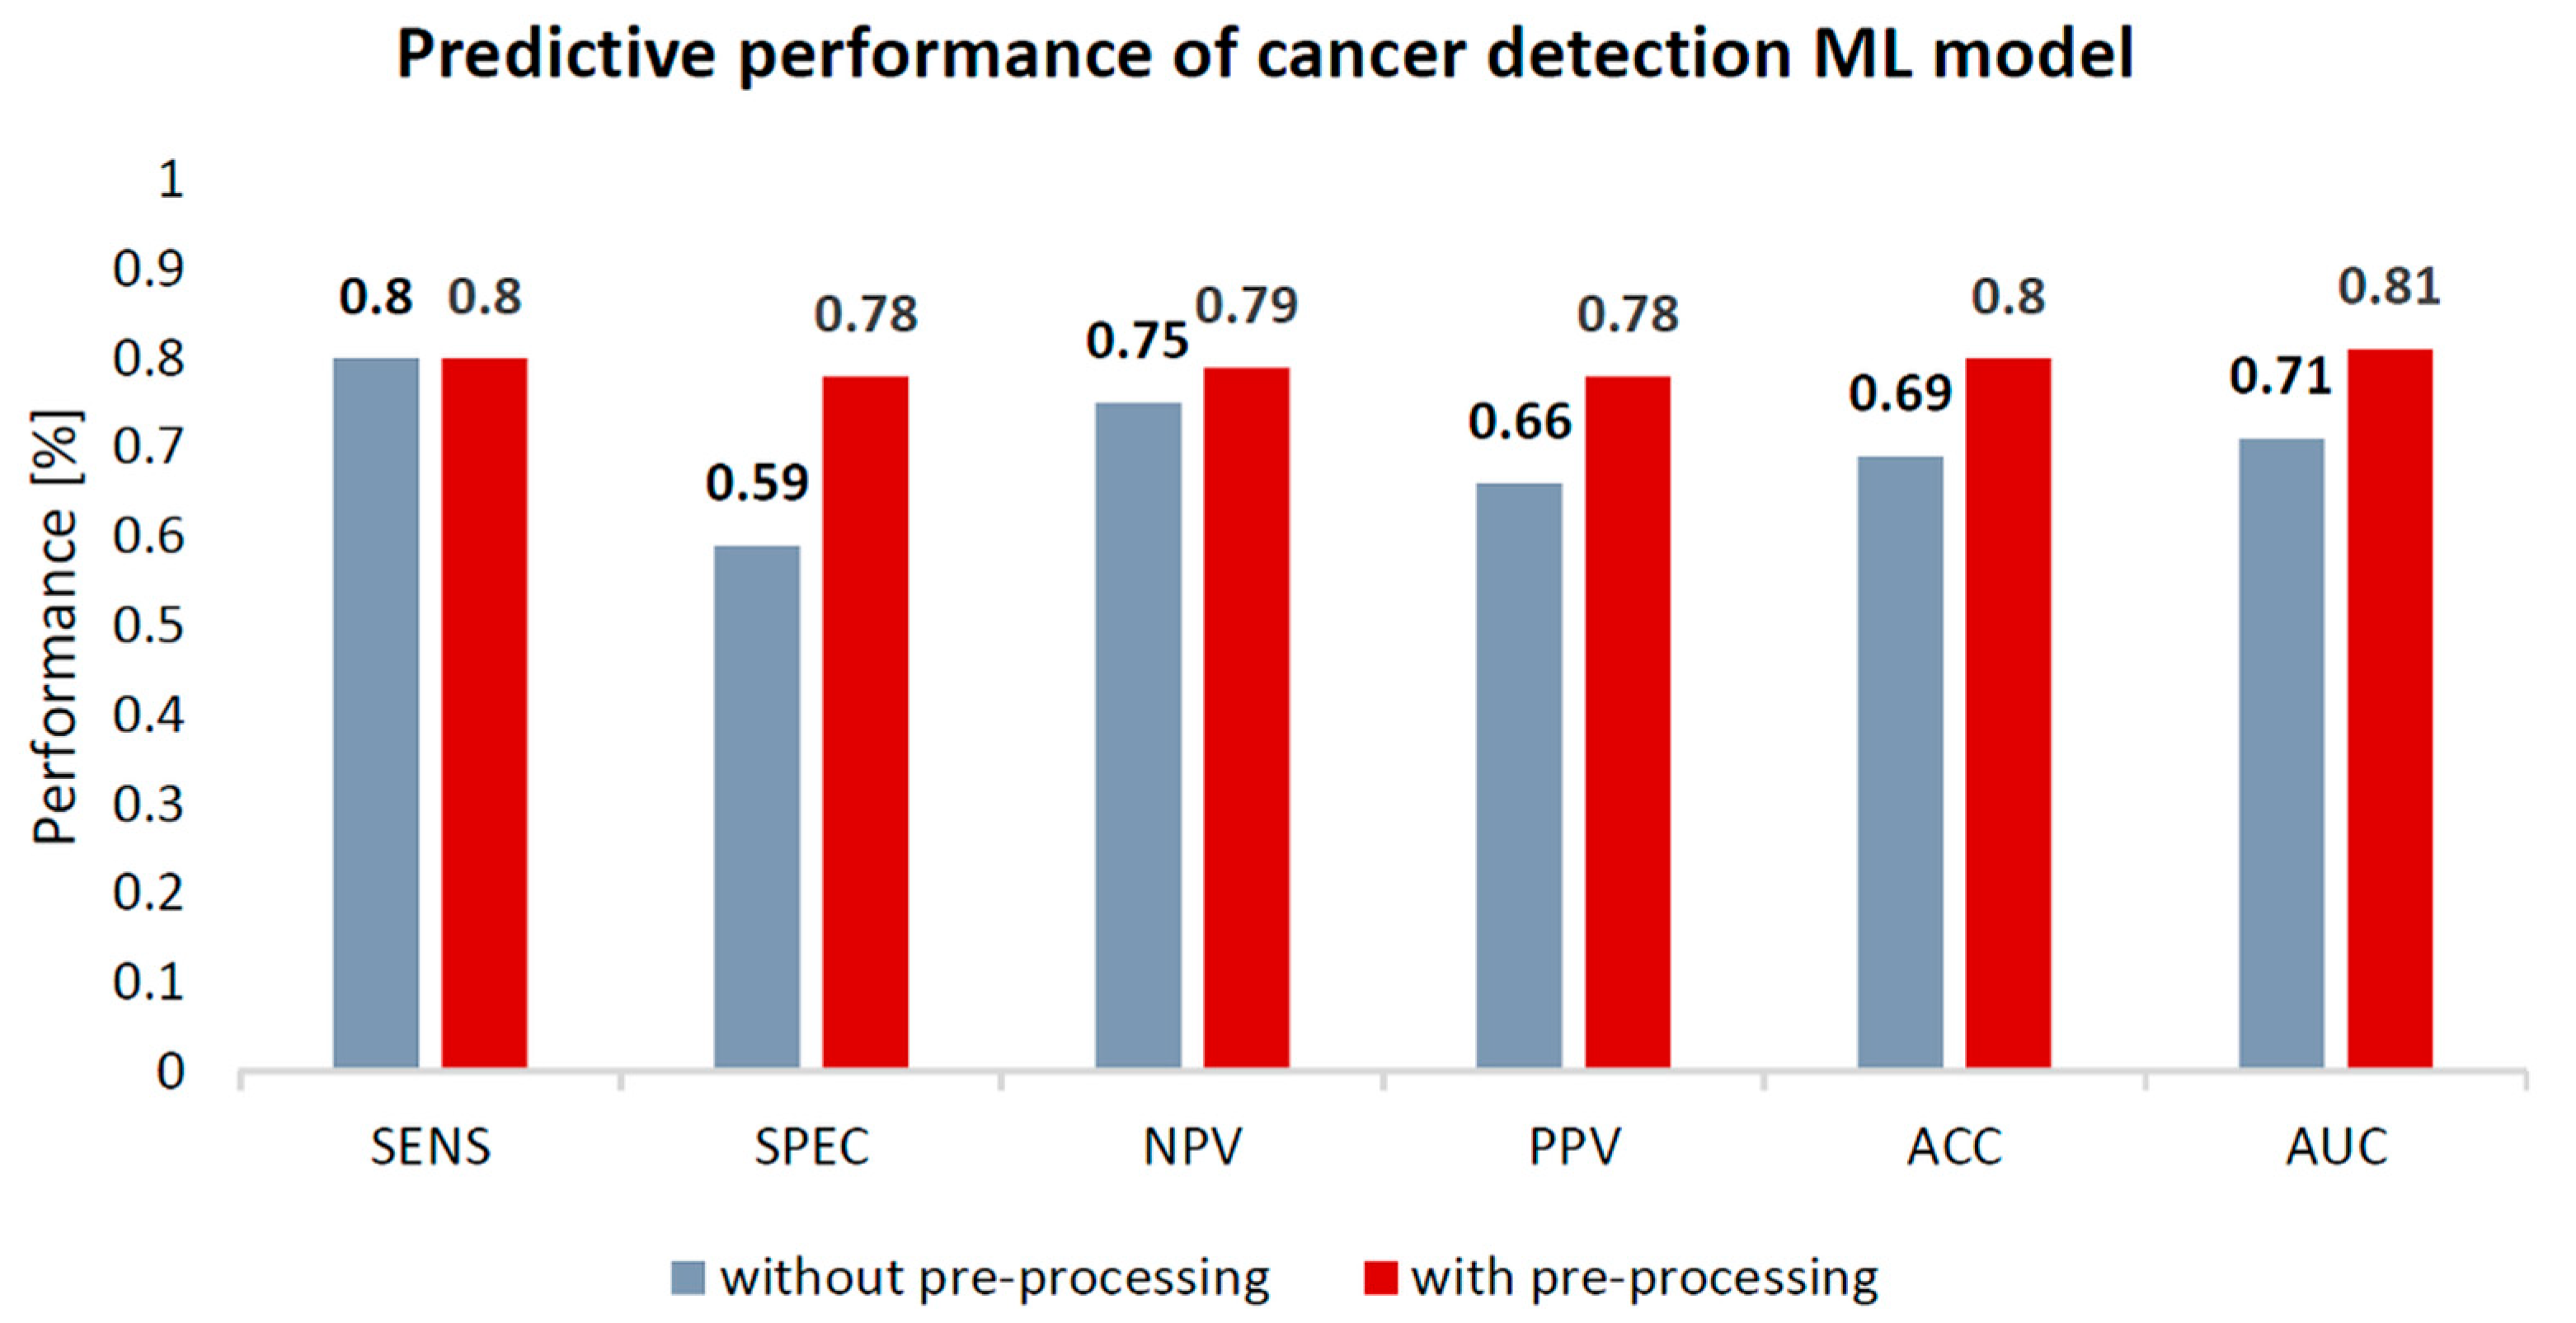

3.2.1. Breast Cancer Detection

| Model | Data Preprocessing | SENS | SPEC | NPV | PPV | ACC | AUC |

| Breast Cancer Detection (Malignant vs. Benign) | No | 80 | 59 | 75 | 66 | 69 | 0.71 |

| Yes | 80 | 78↑ | 79↑ | 78↑ | 80↑ | 0.81↑ |